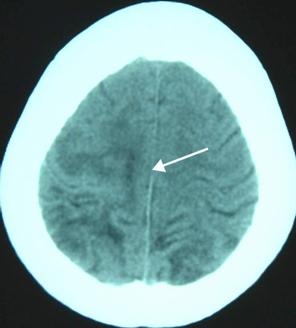

這一次,比在南昌好的是,終於查到了病因——父子兩人其實並不是得了什麼腦瘤,而是——中樞神經係統裂頭蚴病。簡單說,是一種寄生蟲病,就是他們某次吃的青蛙裡有一種叫裂頭蚴的寄生蟲進入了他們的身體,並隨著血液進入了大腦,然後產生瞭如噴射狀嘔吐、抽搐、昏厥、癲癇等症狀。

找到病因後,治療相對來說就簡單一些——做手術,將在腦子裡的寄生蟲取出來。於是,兩個腦部手術,一下讓我的鄰居家成了赤貧狀態,雖然鄰裏也會慰問一些,但終究杯水車薪。而最讓人遺憾的是,手術後,腦部創傷是永久性且不可逆的,所以癲癇成為了他們伴隨一生的痛。

它是某些種類的絛蟲在一個被稱為“中絛期”的發育階段的幼蟲的總稱。雖然還沒有發育完全,裂頭蚴在外形上已經與成蟲頗為相似,而且由於運動能力很強,裂頭蚴給寄生宿主帶來的傷害常常要超過它們的成蟲。裂頭蚴一般寄居在蛙類和蛇類體內,爆炒也不會死,患病後可通過手術治療,但術後依然會有症狀性癲癇,經常突然倒地抽搐。

人體並非迭宮絛蟲或是裂頭蚴的適宜宿主,但它們卻可以給人體帶來很大的傷害。尤其是裂頭蚴,能在人體不同部位間穿行,可能帶來的損傷遍布全身。由裂頭蚴引起的疾病統稱為裂頭蚴病,根據發病的部位,又可以大致劃分為眼、皮下、口腔面部、腦和內臟五大類。在中國,眼裂頭蚴病的發病率最高,症狀也頗為恐怖,病人的眼部會出現腫塊並伴隨各種嚴重不適。如果裂頭蚴侵入的部位是眼球,甚至可能導致失明。有時,裂頭蚴會從患處“爬”出來,不少重口味故事中“眼睛裡面爬出一條蟲子”的情節大概就是源於這個症狀。